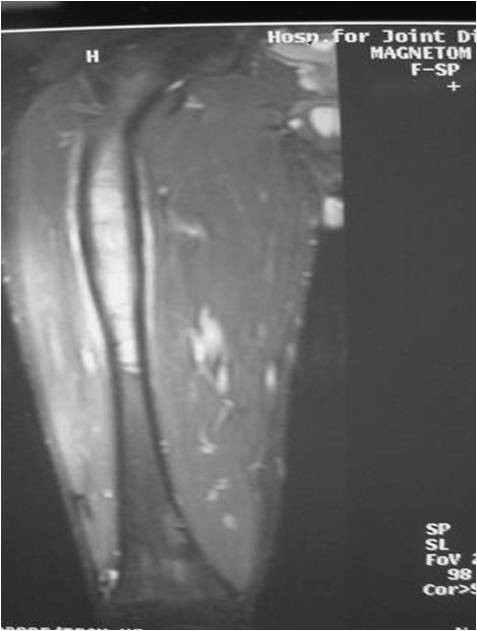

- Most protocols administer preoperative chemotherapy then surgery is performed. Surgery is followed by several courses of postoperative chemotherapy.

- Ewing sarcoma responds well to chemotherapy. Often there is a dramatic reduction in size of the tumor.

- Most common chemotherapy agents utilized include as of 2008: Vincristine, Adriamycin, Cyclophosphamide, Actinomycin-D, Ifosfamide, Etoposide

- Surgical resection

- Limb sparing surgery whenever feasible unless there will be a large leg length discrepancy that can not be accomodated for with surgery

- Response to preoperative chemotherapy: Greater than 90% tumor necrosis (Good response) correlates with a better prognosis